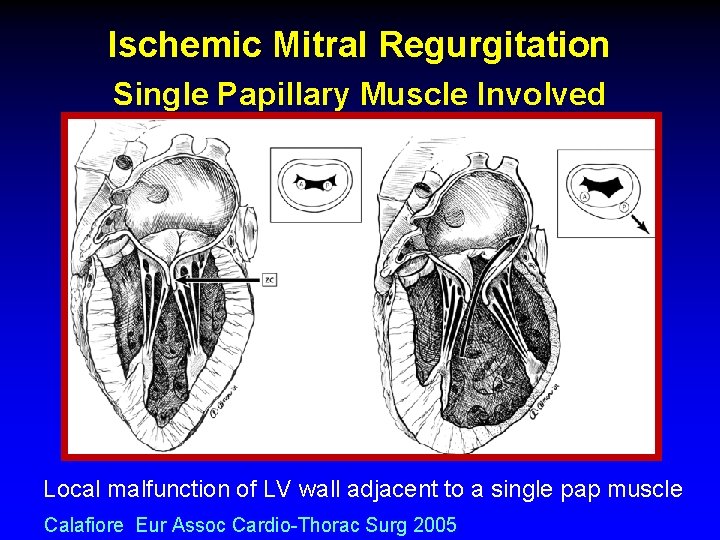

Ischemic Mitral Regurgitation Single Papillary Muscle Involved Local malfunction of LV wall adjacent to a single pap muscle Calafiore Eur Assoc Cardio-Thorac Surg 2005